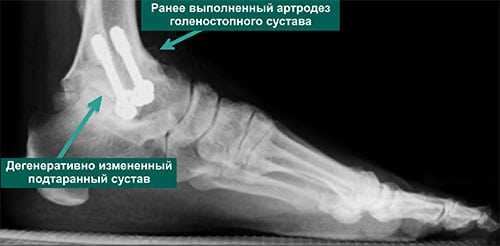

- Магнитно-резонансная томография позволяет увидеть признаки артрита голеностопного и/или подтаранного суставов, которые не видны на рентгенограммах (рис. 3)

- При наличии артрита подтаранного сустава тотальное эндопротезирование голеностопного сустава будет предпочтительней артродеза

- Выполненный ранее артродез голеностопного сустава при условии интактности малоберцовой кости